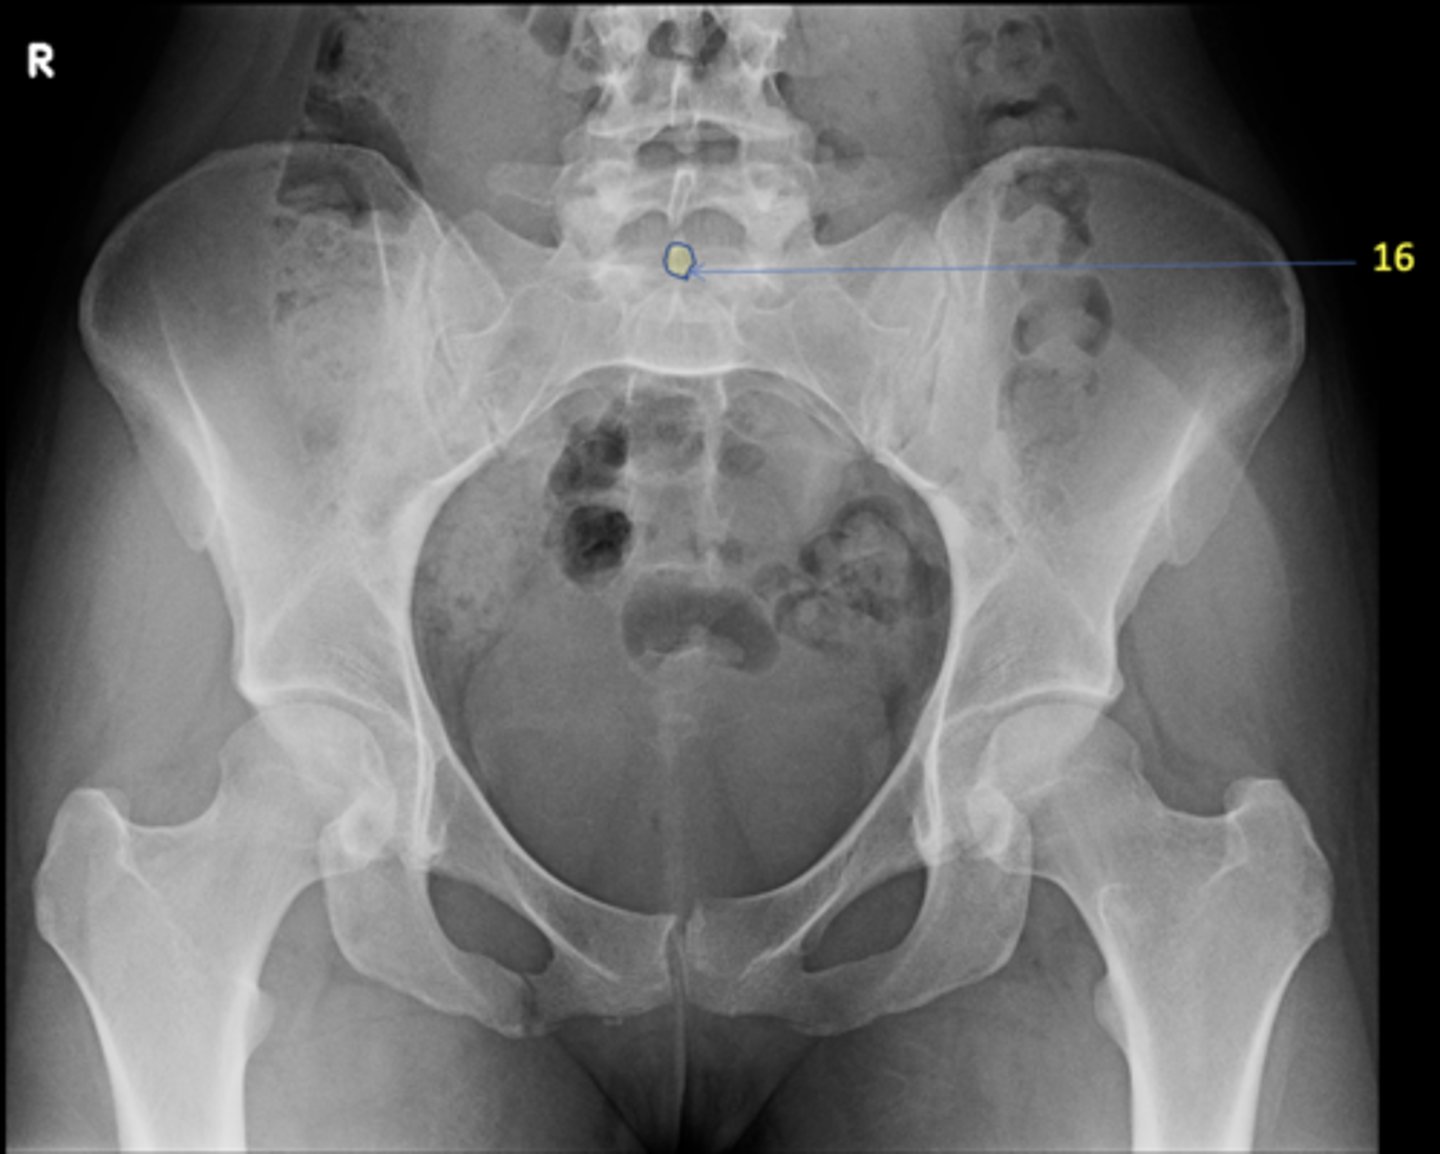

1

AP pelvis

View?

<p>View?</p>

S1 tubercle

ID 16

<p>ID 16</p>